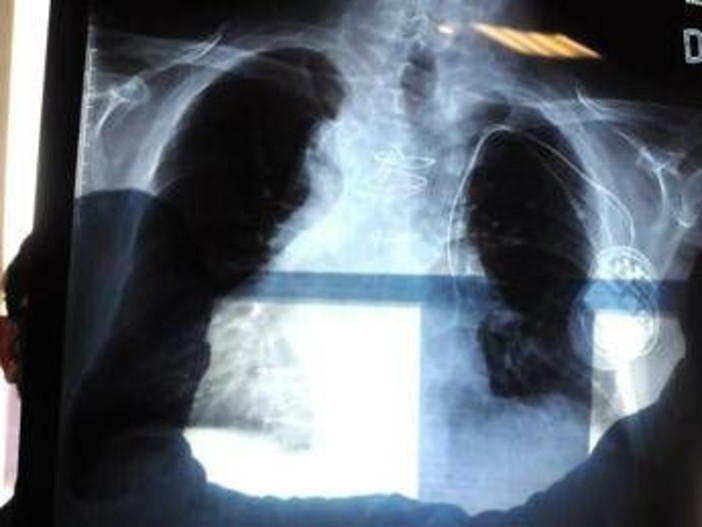

(Adnkronos) - Una diagnosi di polmonite è fonte di preoccupazione a qualsiasi età. Questa malattia, infatti, "è una causa di ricovero ospedaliero da sempre e, purtroppo, anche causa di morte. Tutti gli anni sono 150mila gli italiani ricoverati e 9mila i decessi. Ma attualmente non registriamo grandi cambiamenti nei numeri, l'epidemiologia è stabile. E come sempre, ogni anno, si registrano complicanze serie che riguardano soprattutto le persone a rischio: gli anziani, i bambini, i pazienti cronici". A fare il quadro per l'Adnkronos Salute è Claudio Micheletto, presidente dell'Associazione nazionale pneumologi ospedalieri (Aipo), in un periodo in cui alcuni casi noti hanno riportato all'attenzione questa patologia, in particolare per la forma interstiziale, come per la morte del maestro Peppe Vessicchio o per il ricovero dell'allenatore del Bologna Vincenzo Italiano.

La polmonite, prosegue il presidente di Aipo, è un'infezione che "può essere localizzata in un punto particolare del polmone. L'ente patogeno più frequente in questo caso è lo pneumococco, contro il quale esiste appunto una vaccinazione. Esistono poi le polmoniti interstiziali che colpiscono il tessuto connettivo del polmone, l'area dove avviene lo scambio, per questo l'infezione può essere molto diffusa e anche bilaterale. E' dovuta prevalentemente a virus, il Covid tra questi, come abbiamo visto durante la pandemia, e ad alcuni batteri. Altro caso abbastanza emblematico è la legionella, oppure i cosiddetti agenti intracellulari, micoplasma e clamidia". L'intestizio, precisa Micheletto, "è il tessuto di sostegno del polmone, dove avviene il passaggio dell'ossigeno e dell'anidride carbonica nel senso contrario, tra gli alveoli e i capillari. Quando questo interstizio viene colpito, lo scambio viene notevolmente ridotto. Ma se il paziente ha la bronchite cronica o è un fumatore, questi spazi sono già compromessi. E quindi può dare casi gravi".

Ma quali sono i segnali d'allarme che indicano una possibile polmonite? "Una polmonite si presenta prevalentemente tosse e febbre", descrive lo pneumologo. Ma la "gravità che causa ospedalizzazione riguarda la difficoltà respiratoria, che può essere altamente rischiosa", conclude.